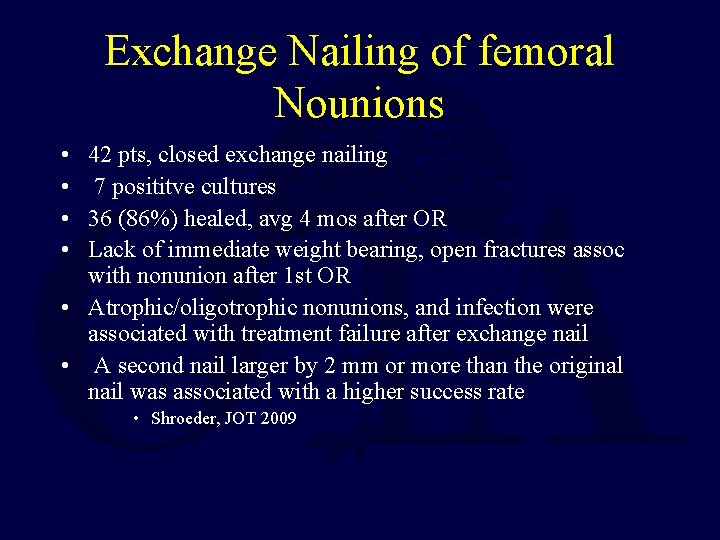

Exchange Nailing of femoral Nounions • • 42 pts, closed exchange nailing 7 posititve cultures 36 (86%) healed, avg 4 mos after OR Lack of immediate weight bearing, open fractures assoc with nonunion after 1 st OR • Atrophic/oligotrophic nonunions, and infection were associated with treatment failure after exchange nail • A second nail larger by 2 mm or more than the original nail was associated with a higher success rate • Shroeder, JOT 2009